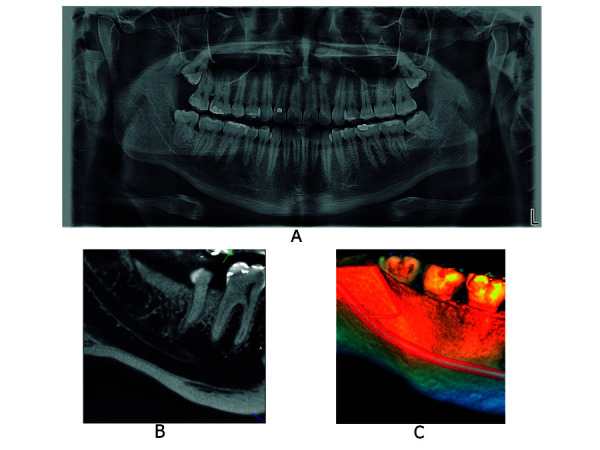

Abstract Image